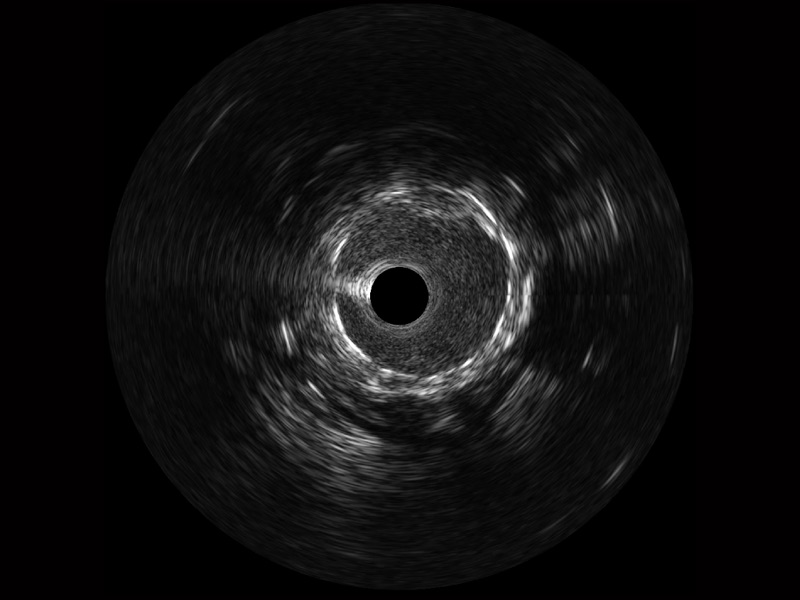

milan米兰宽频IVUS图像

传统IVUS图像

对比传统IVUS导管成像,milan米兰宽频IVUS图像的近场支架梁显影更细腻,远场中膜外血管仍清晰可辨,兼顾远中近,兼顾分辨力与穿透深度